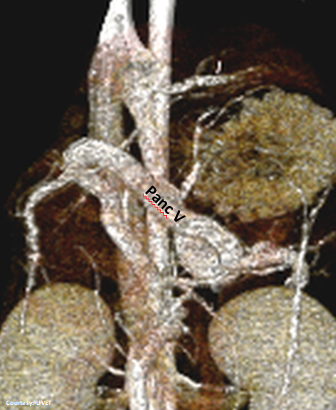

“aLGC +RGV”

Aberrant Left Gastric-Caval Shunt with Right Gastric Vein contribution

Alternate (Pancreatic vein contribution as well): “aLGC +RGV +PancV”

WEISSE 2022

slide16